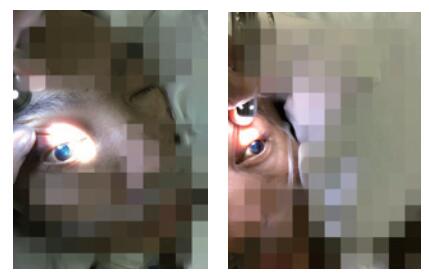

患者,男,31岁,既往体健。因“间断发热、咳嗽10 d,昏迷16 h”于2016年12月9日入院。患者2016-11-30无诱因出现咳嗽、发热,抗感染治疗3 d后,症状好转。2016-12-6患者再次出现上述症状,最高体温38℃,伴头痛。2016-12-8 19:31于本院就诊期间出现意识模糊,瞻妄,次日02:15患者深昏迷,呼之不应。查体:体温38.5℃,脉搏131次/min,呼吸29次/min,血压126/56 mmHg(1 mmHg=0.133 kPa), 心、肺、腹未见异常。专科情况:深昏迷,双侧瞳孔不等大,左侧d=5.5 mm, 右侧d=6.0 mm, 双侧对光反射消失,疼痛刺激无反应,角膜反射未引出,脑神经查体不合作,四肢肌力查体不合作,双上肢肌张力高,双下肢肌张力正常,双侧膝、跟腱反射亢进,踝阵挛,颈强直,克氏征阳性、布氏征阳性。颅脑CT示双侧侧脑室低密度影,颅内感染?双侧侧脑室扩张。血常规:白细胞15.43×109/L,中性粒细胞百分比4.62%;降钙素原3.74 ng/mL, 12月9日行腰椎穿刺抽出淡黄色微混脑脊液,压力>300 cmH2O(1cmHg=0.098kPa), 脑脊液常规:细胞总数864 ×106/L,白细胞818×106/L,多核细胞80%,单核细胞20%,生化:氯113.3 mmol/L,葡萄糖1.00 mmol/L,总蛋白258.0 g/L,革兰染色、墨汁染色、抗酸染色阴性,脑脊液培养结果阴性。血培养结果示:肺炎链球菌。诊断为化脓性脑膜炎,病原菌为肺炎链球菌。给予降颅压,抗感染治疗后,症状好转,2016-12-12患者疼痛刺激有反应。2016-12-20神志转清,可按指令发出动作,但遗留有双侧动眼神经损伤,表现为双侧瞳孔散大,双侧对光反射消失,双侧眼睑下垂,左侧明显,双侧瞳孔各方位(除外展位外)运动不良;此外,合并双侧视神经、左侧面神经损伤,表现为无光感,左侧额纹消失,左侧鼻唇沟略浅。2016-12-26患者恢复部分光感,但视野缺损,无法分辨颜色。双侧动眼神经损伤及左侧面神经损伤未见明显改善,查体脑膜刺激征仍阳性。2016-12-15复查颅脑CT较前无明显变化。2016-12-27颅脑磁共振示脑积水,颅底感染,考虑患者动眼神经及其余脑神经损伤与高颅压压迫脑神经及颅底感染侵及脑神经有关,建议患者外院行脑室穿刺引流术进一步治疗。

2 讨论肺炎链球菌目前为成人化脓性脑膜炎最主要病原菌,大约占到所有病原菌的50%~80%[1-2]。Jit[3]研究提示肺炎链球菌脑膜炎出院患者中,30%~40%的患者都有后遗症,包括智力受损、瘫痪、癫痫发作、听力受损。这些损伤可能与炎症致血管改变导致的脑梗死,脑出血,脑脓肿,血管炎,血栓形成有关[2, 4]。而肺炎链球菌脑膜炎引起动眼神经损伤及其他脑神经损伤的病例极少。复习文献,通常动眼神经损伤考虑以下几方面原因:①颅内损伤,通常由于支配动眼神经核、动眼神经副核的血管发生血管炎或血管痉挛致动眼神经损伤。②颅外损伤,通常与高颅压压迫脑神经有关,常同时涉及第二、三、六、七、八对脑神经,这些脑神经均穿过蛛网膜下腔区域。③颅底感染很容易侵及脑神经,同时晚期形成颅底蛛网膜广泛粘连影响脑脊液回流,这在结核性脑膜炎及隐球菌性脑膜炎中多见,而肺炎链球菌性脑膜炎很少累及颅底感染[5-7]。该患者起病急,临床表现典型,结合病史及辅助检查,考虑化脓性脑膜炎诊断明确,病原学考虑肺炎链球菌。但患者意识恢复后逐渐出现动眼神经、面神经、视神经等多对脑神经损伤。对于该患者,动眼神经损伤同时累及视神经、面神经等多对脑神经损伤,持续脑积水状态,且影像学可见明显的颅底感染,故考虑该患者的脑神经损伤与高颅压状态压迫脑神经及颅底感染侵及多对脑神经有关。最终建议患者行侧脑室穿刺引流、脑室-腹腔分流术等解除高颅压状态。

| 图 3 上睑下垂、眼球外展位、对光反射消失提示动眼神经损伤 |